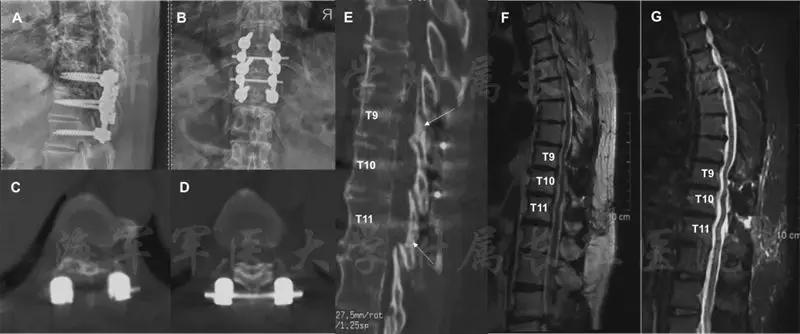

58岁女性患者,由于双下肢麻木、疼痛和行走障碍伴小便障碍两年,加重一月来我院就诊。术前X线片提示在T9/10h和T10/11处存在高密度影。进一步CT检查确诊为该节段黄韧带骨化,呈结节型和扩大型压迫脊髓,最高脊髓侵占率达71.61%(图5)。

图5 病人术前影像学资料

在完善进一步检查后为该病人实施“龙门吊”脊髓后方减压术。整个手术过程分为病人术前准备,术中暴露,复合物游离,“吊桥”安装和最后的提拉。图6是术中的实际操作图和示意图。整个手术过程,病人电生理状态良好。

图6 该病人手术示意图和术中操作图

在术后6个月的随访中,病人未出现手术相关的的并发症。病人的肌力由术前的1恢复到最后随访的4.下肢运动和感觉障碍也得到了明显的恢复,病人可以不需要辅助独立行走。病人的泌尿系统功能也得到了明显的改善。JOA评分恢复率在随访的3月和6月分别为50%和75%。术后影显示脊髓获得了充分的减压,脑脊液带也获得了满意的恢复。在最后的随访中,X线提示“吊桥”位置良好,患者植骨也得到了很好的融合。

图7 患者术后6月随访影像学资料